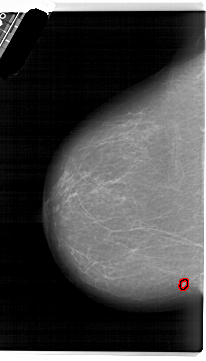

A_1639_1.RIGHT_MLO

RIGHT_MLO LINES 5971 PIXELS_PER_LINE 3856 BITS_PER_PIXEL 12 RESOLUTION 43.5 NON_OVERLAY

FILE: A_1639_1.LEFT_MLO.OVERLAY

TOTAL_ABNORMALITIES 1

ABNORMALITY 1

LESION_TYPE MASS SHAPE IRREGULAR MARGINS ILL_DEFINED

ASSESSMENT 4

SUBTLETY 2

PATHOLOGY MALIGNANT